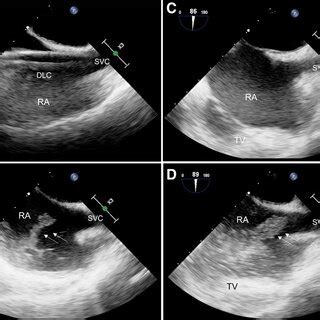

So, why is this bicaval view so crucial? Think of the heart as a bustling city, and the vena cava are the highways bringing in all the traffic (blood) from the rest of the body. The bicaval view gives us a panoramic view of these highways as they enter the heart’s main station (the right atrium). This view is your go-to for checking the size and shape of these major vessels and how they function. This is especially vital when checking for clots, which can be deadly. It also helps in assessing the pressure within the right atrium, a key indicator of heart health. Furthermore, it gives a good look at the tricuspid valve, ensuring it’s working properly. This view is also super helpful in assessing patients with shortness of breath, chest pain or other symptoms related to heart problems, the bicaval view can provide crucial insights.

Now, let’s get into the nitty-gritty of how to get the perfect view. First, remember the patient should be lying on their left side, which is known as the left lateral decubitus position. This helps bring the heart closer to the chest wall. The probe itself is the magic wand, and the specific type you use (usually a phased array) is designed for this kind of imaging. Then comes the tricky part: the probe position. Imagine you are trying to catch the sun at the optimal angle. The goal is to position the probe under the sternum (the breastbone), aiming slightly towards the patient’s right shoulder. The idea is to align the ultrasound beam with the vena cava so you can see them clearly as they enter the right atrium. Be patient and adjust slightly until you get the best image. The orientation marker on the probe is your best friend here; it should point toward the patient’s right. It may take some practice, but you’ll get the hang of it.

Alright, let’s break down the process step-by-step for the bicaval view echo probe position . First, you’ll need the right equipment: an ultrasound machine, the right kind of probe (usually a phased array), and some acoustic gel (that stuff that makes everything glide smoothly). The patient should be positioned in the left lateral decubitus position. This positioning moves the heart closer to the chest wall, making it easier to get clear images. Now, apply the acoustic gel liberally to the probe head. This helps eliminate air pockets and ensures good contact with the skin. Place the probe just below the sternum, aiming towards the patient’s right shoulder. Gently angle the probe and try to visualize the right atrium and the vena cava. Remember to keep the probe flat against the chest wall to get the best contact and minimize any loss of image quality. Slight adjustments are often necessary to find the sweet spot, the one where the images are super clear. Scan through the various angles to see which one gives you the best picture of the superior and inferior vena cava entering the right atrium.